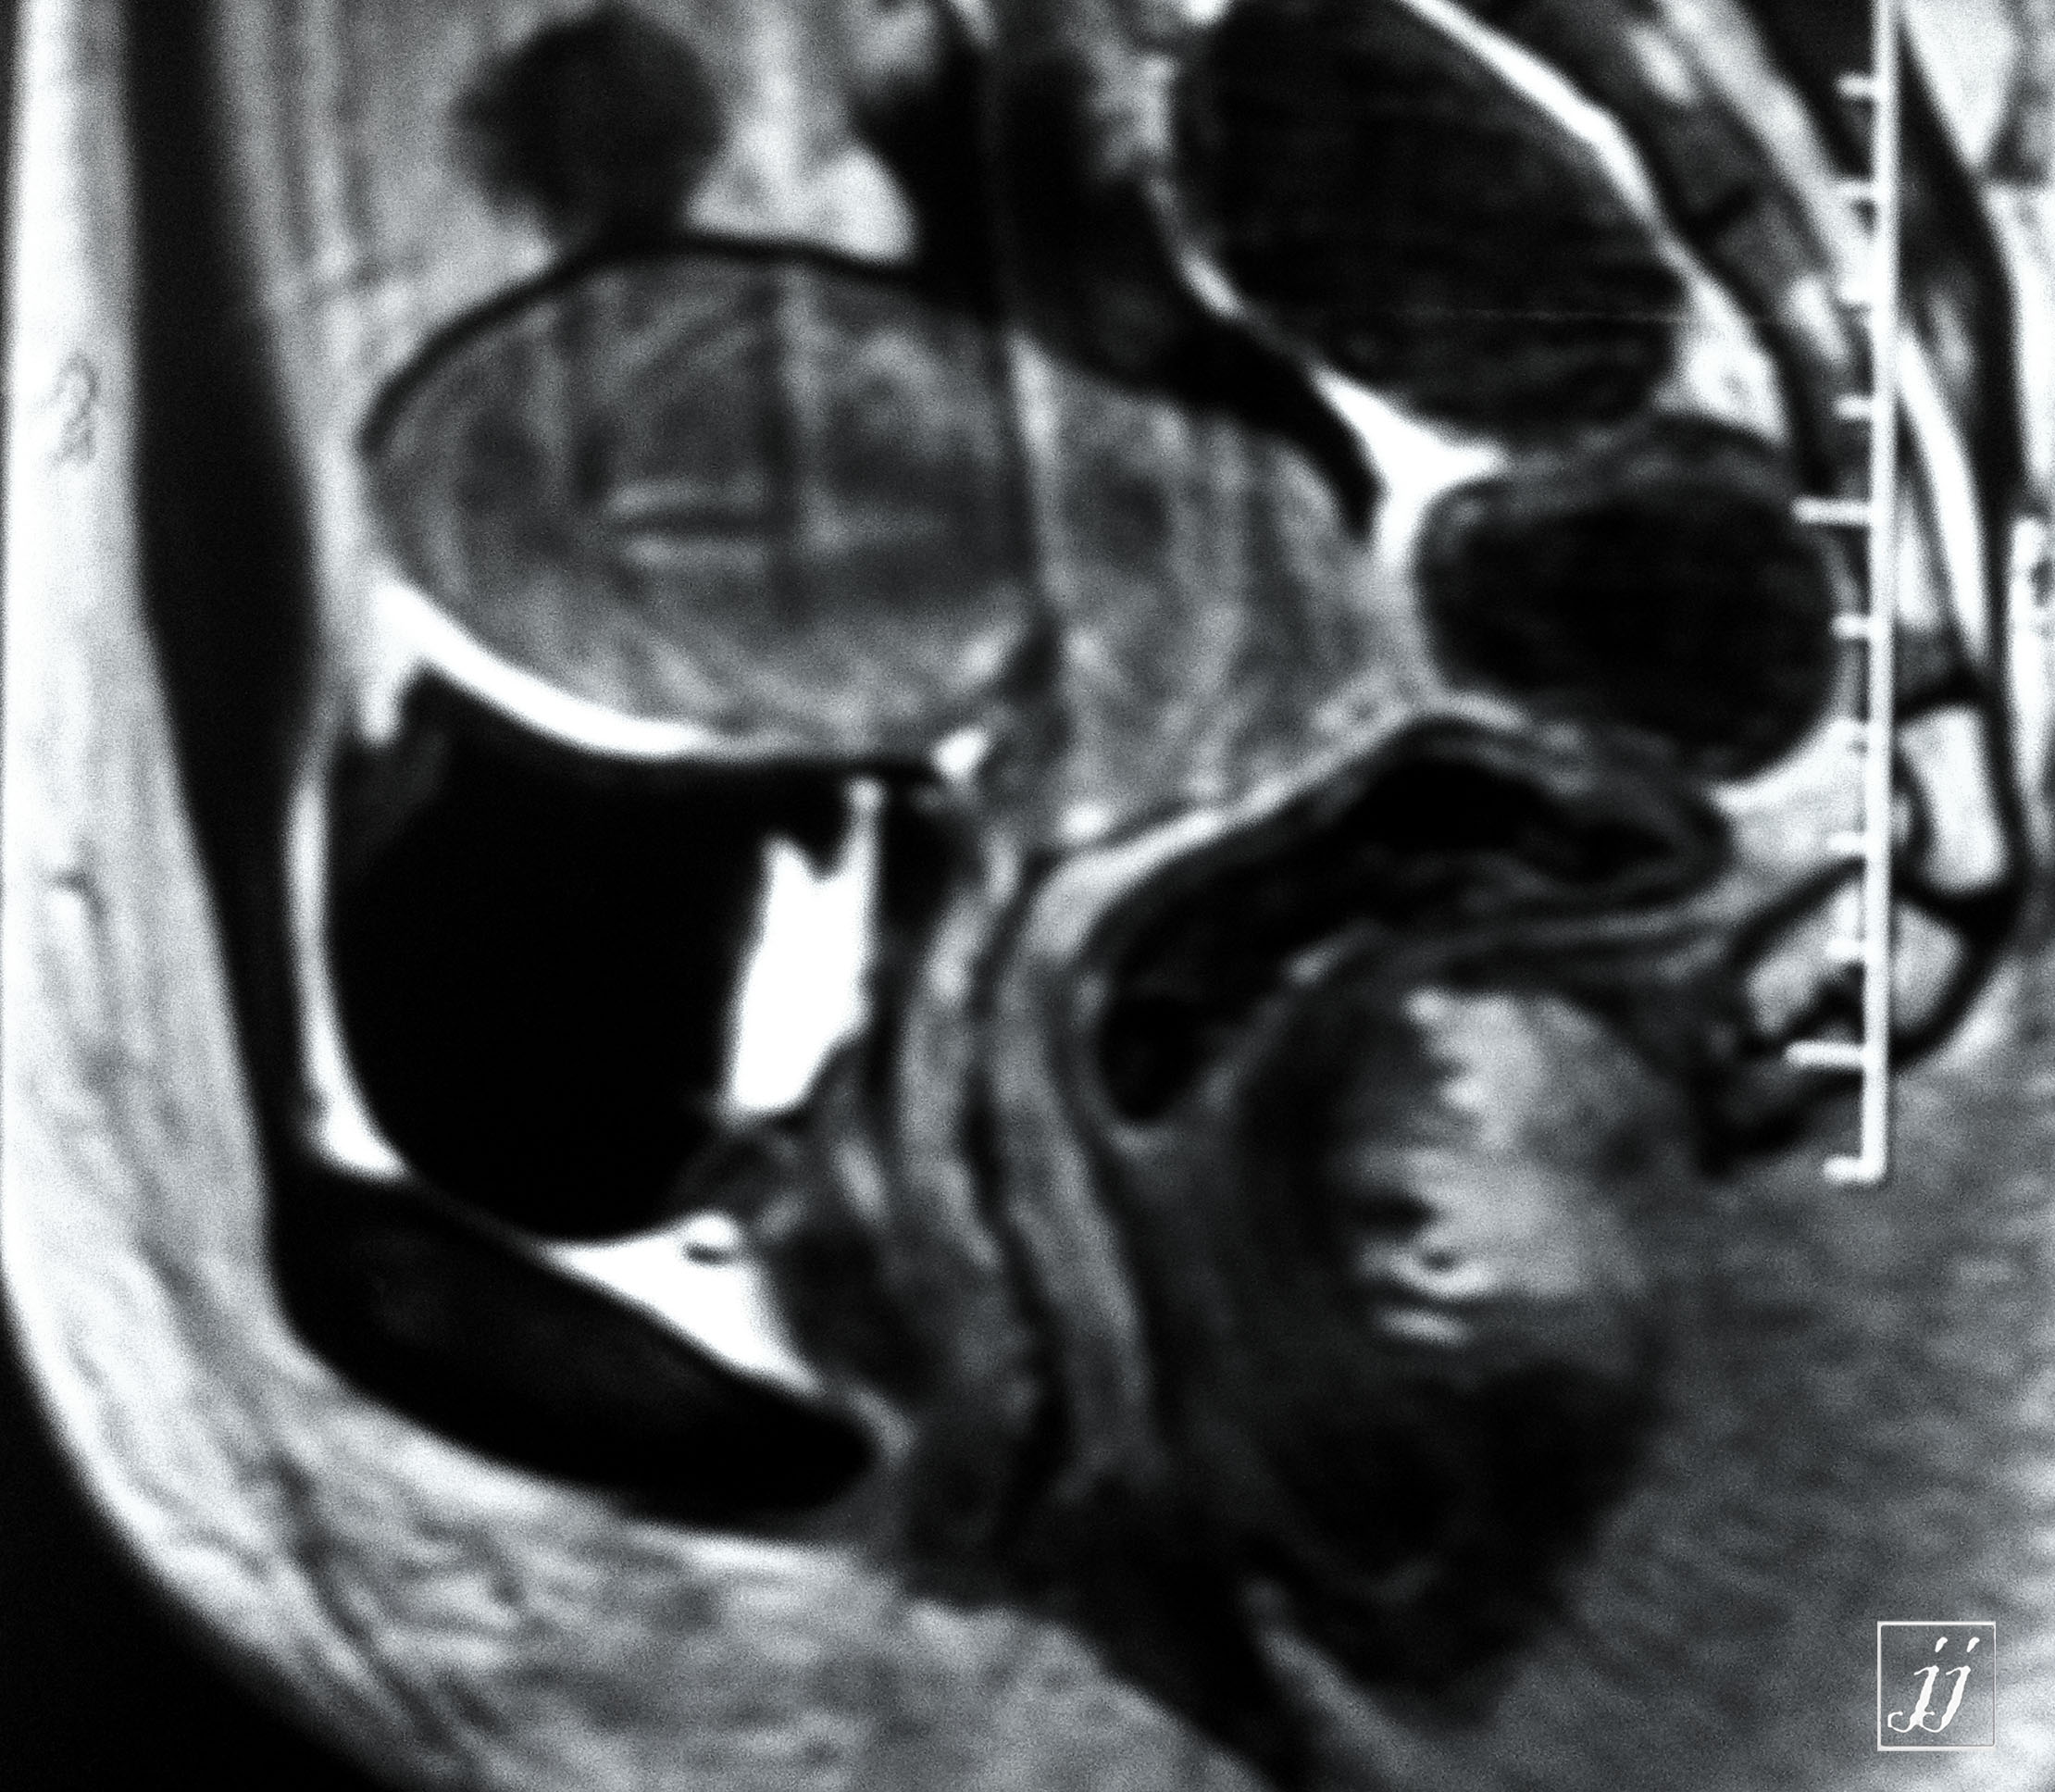

Abdomen- left side endometriosis vs dermoid cyst (6)